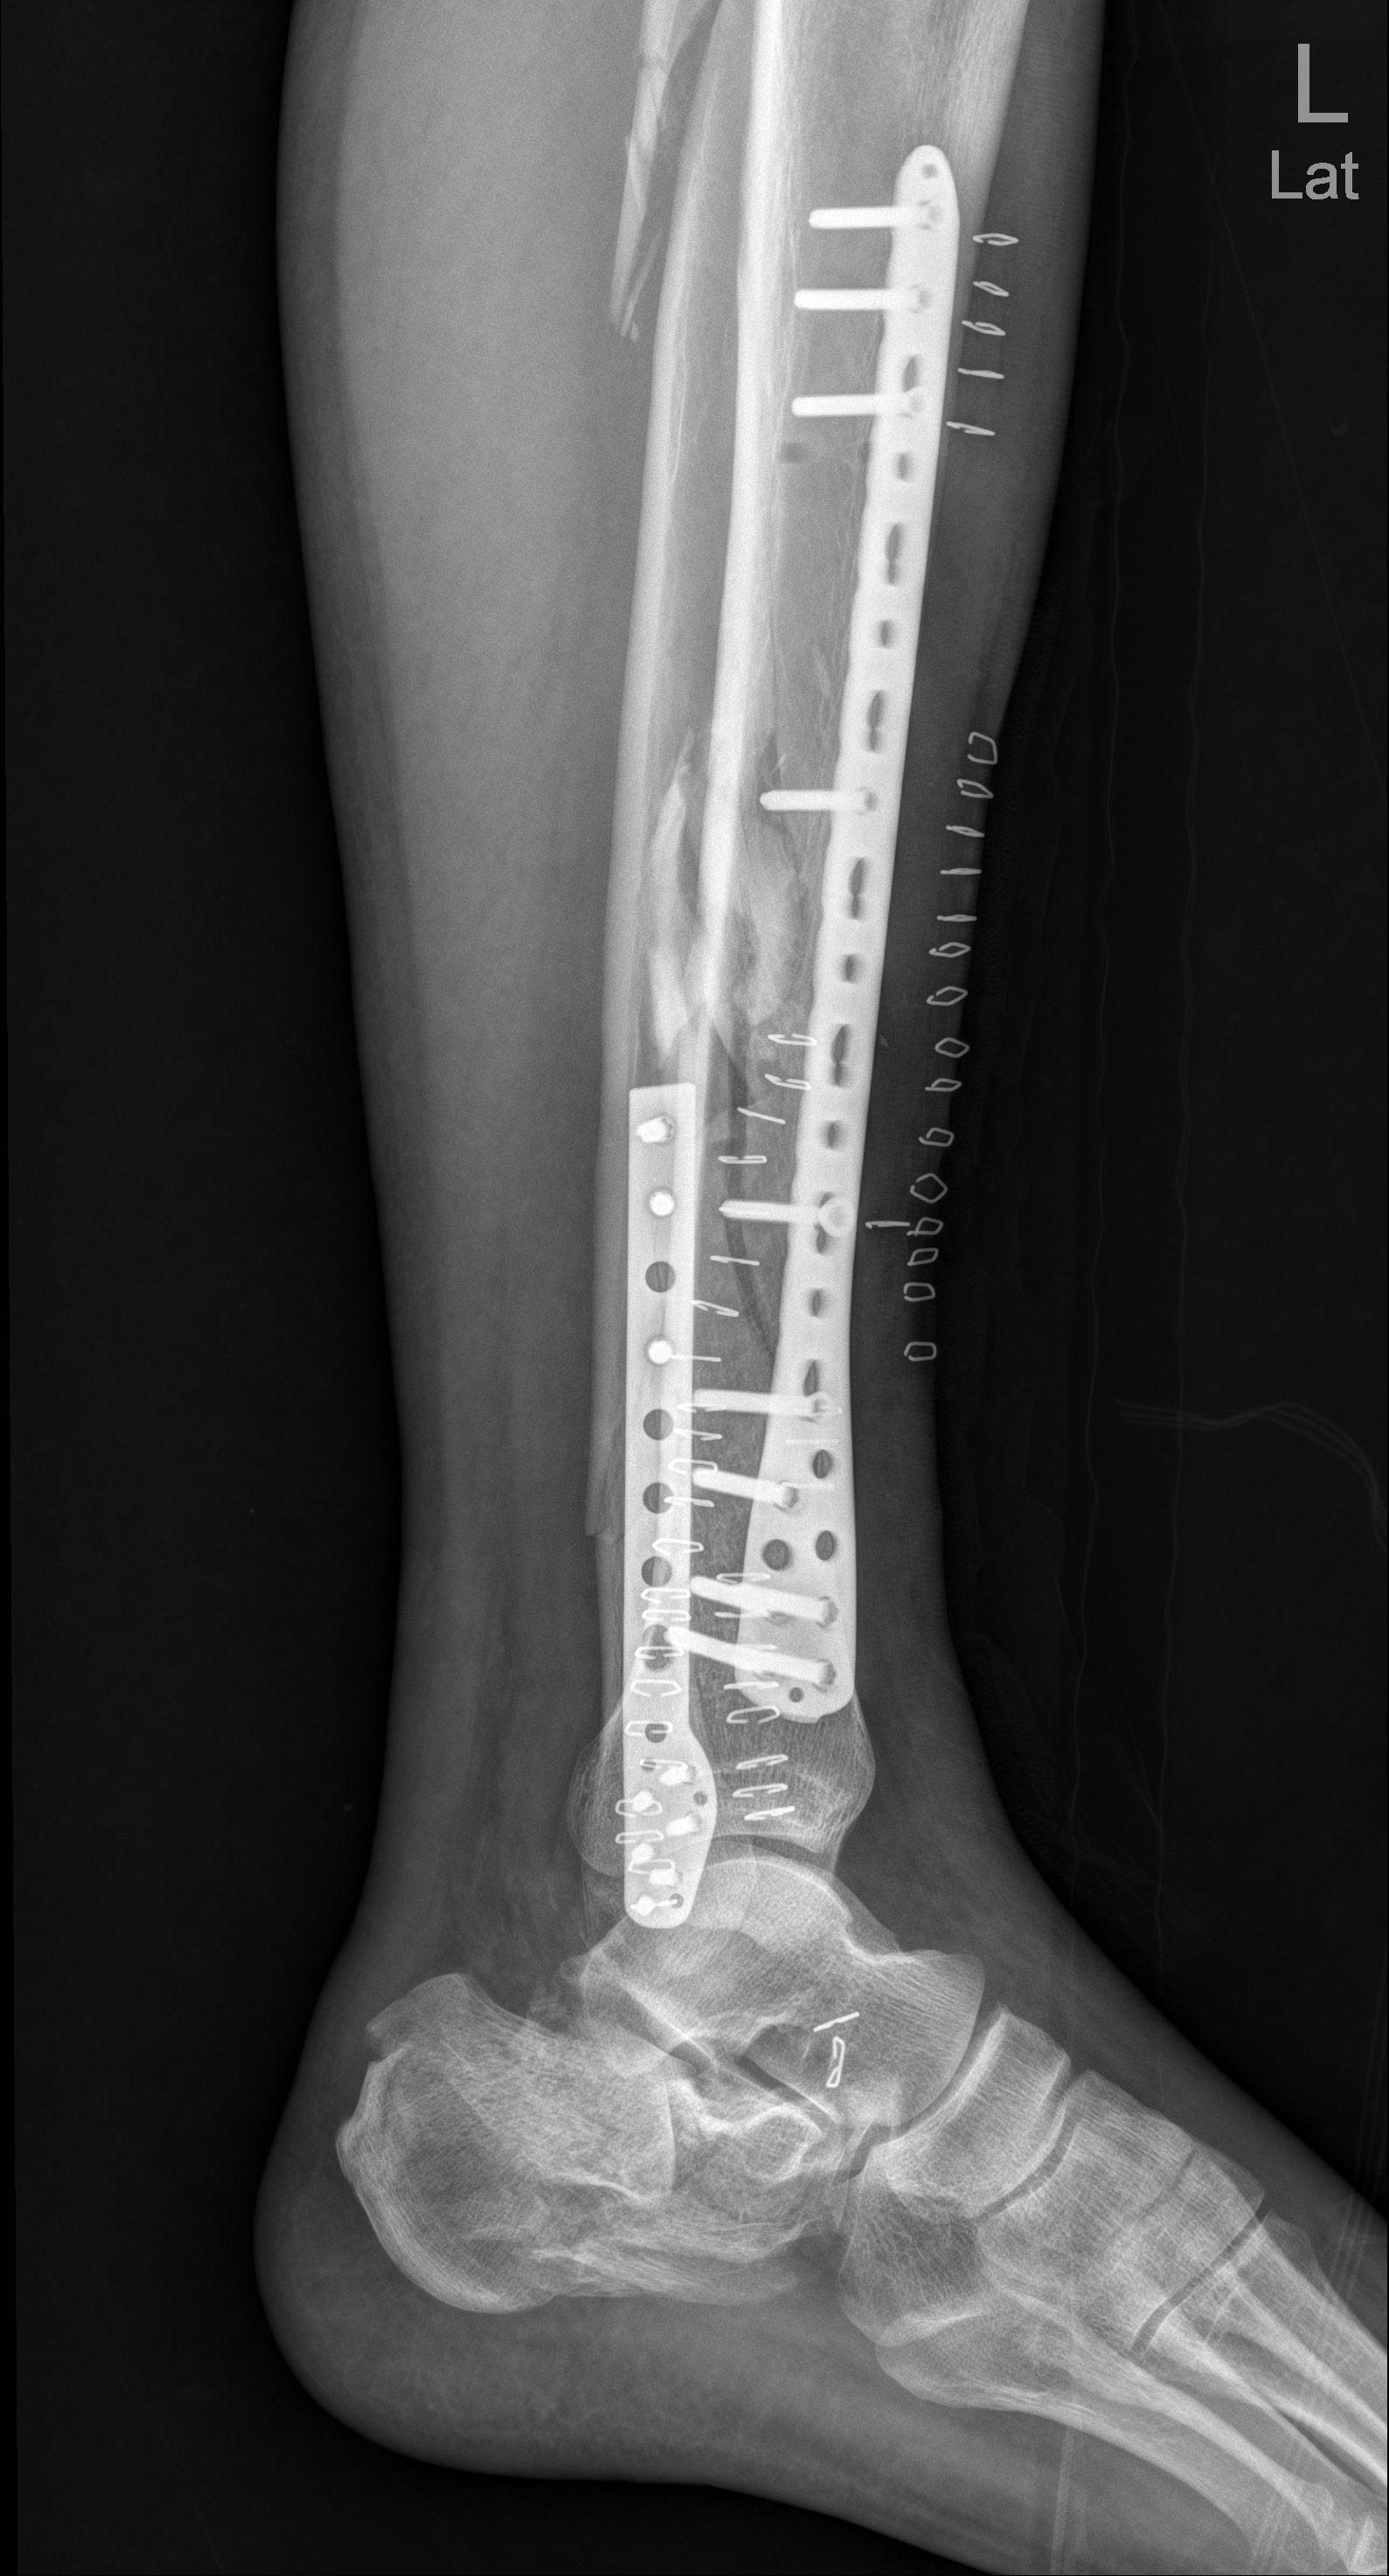

园区老板殴打我,并一脚踩断我的左胫骨,打了10几分钟,随后把我丢在保安室。

我在里面痛了 8–9 小时才被人接出,然后送去医院,一直没交钱,医院就停药了,期间刘*坤怕我从医院跑,还偷偷把我身份证及所有证件哪些拿走,后面找他们要证件回国治疗不同意,自己想办法雇了壹*集团的护卫偷偷把我从医院接出去了,导致20多天没有及时治疗,这个事情不会这么结束的,证据我一大堆,有本事回国!